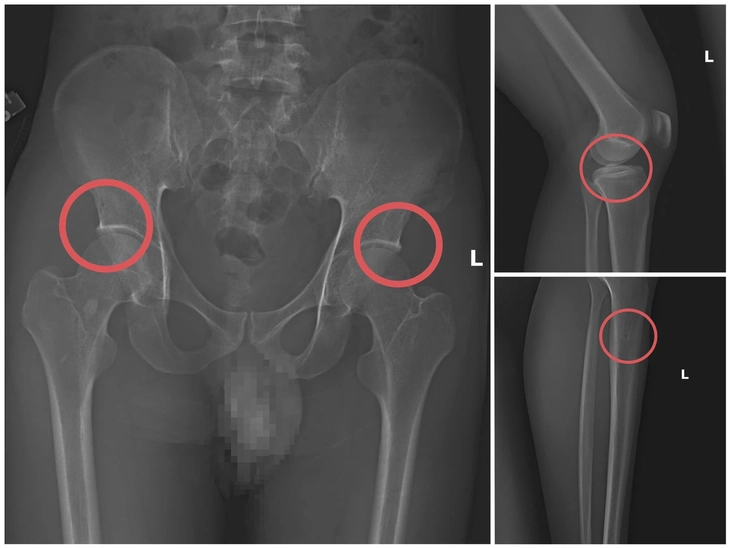

Theo đó, thông qua các tài liệu thu thập được, cơ quan Cảnh sát điều tra làm rõ đối tượng Tạ Minh Châu (SN 1995, nguyên cán bộ Trung tâm Y tế huyện Cẩm Khê) là kẻ chủ mưu, cầm đầu. Lợi dụng thời gian dài công tác trong ngành y và am hiểu sâu cấu tạo xương – khớp, cũng như cơ chế chi trả bảo hiểm đối với các thương tích gãy xương giá trị cao, Châu đã dựng lên một quy trình trục lợi bài bản, từ việc vận động mua bảo hiểm, tổ chức gây thương tích, đến hợp thức hóa hồ sơ bệnh án để chiếm đoạt tiền của các công ty bảo hiểm.

Đáng chú ý, Châu trực tiếp thực hiện hành vi tiêm thuốc mê, rồi dùng kim tiêm, búa, đinh để tác động vào xương người mua bảo hiểm, tạo nên các vết nứt, vỡ xương tương tự tai nạn thật. Khi thương tích đã tạo xong, Châu tiếp tục hướng dẫn các đối tượng dựng hiện trường giả như điện giật ngã, trượt chân ngã suối nhằm hợp thức hóa bệnh án và hoàn thiện hồ sơ yêu cầu chi trả.

Theo đánh giá của Giám đốc Công an tỉnh Phú Thọ, thủ đoạn này vừa tàn nhẫn, vô nhân tính, coi thường sức khỏe, tính mạng của người tham gia, vừa được tính toán kỹ để gây thương tích đúng vị trí có mức chi trả cao, khiến các công ty bảo hiểm khó phát hiện dấu hiệu gian dối.